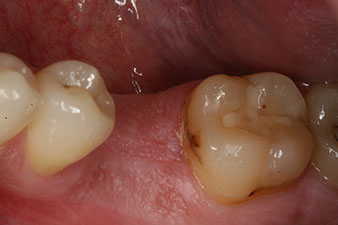

Bei einem 28-jährigen Patienten mit ausgeprägter Raucheranamnese musste Zahn 36 als Folge einer rezidivierenden apikalen Parodontitis extrahiert werden.

Wegen der weitgehend intakten Nachbarzähne kam als Lückenversorgung nur ein Implantat in Frage.

Sechs Wochen nach Extraktion zeigte sich jedoch nach Präparation des Mukoperiostlappens im Bereich der ehemaligen mesialen Alveole eine unvollständige Ossifikation.